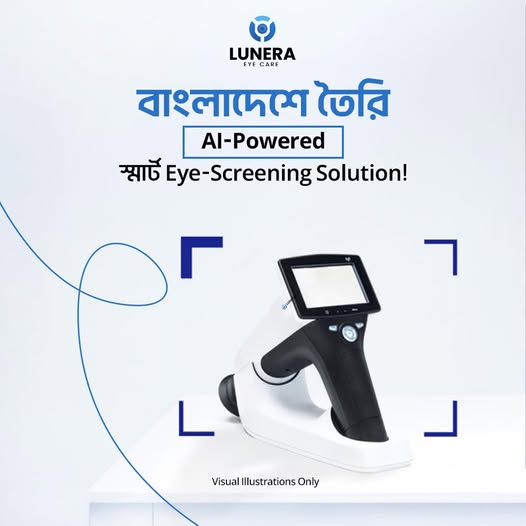

Bangladesh’s First AI-Powered Portable Eye Screening Solution

With smartphone-based retinal imaging, deep learning, and a cloud-powered backend, Lunera delivers instant, reliable results in seconds. Unlike traditional scanners, it requires minimal training, works in low-resource settings, and is designed to be economically accessible.

Lunera is Bangladesh’s first portable, AI-powered eye-screening device, designed to make early detection of vision-threatening diseases simple, accessible, and affordable for all. Built for low-resource environments — yet powered by cutting-edge deep learning —Lunera enables healthcare providers across the country to screen for Diabetic Retinopathy (DR) and other retinal conditions in seconds, without the need for traditional bulky equipment or specialist interpretation.

1. Capture

A healthcare worker attaches Lunera to a smartphone and takes retinal images.